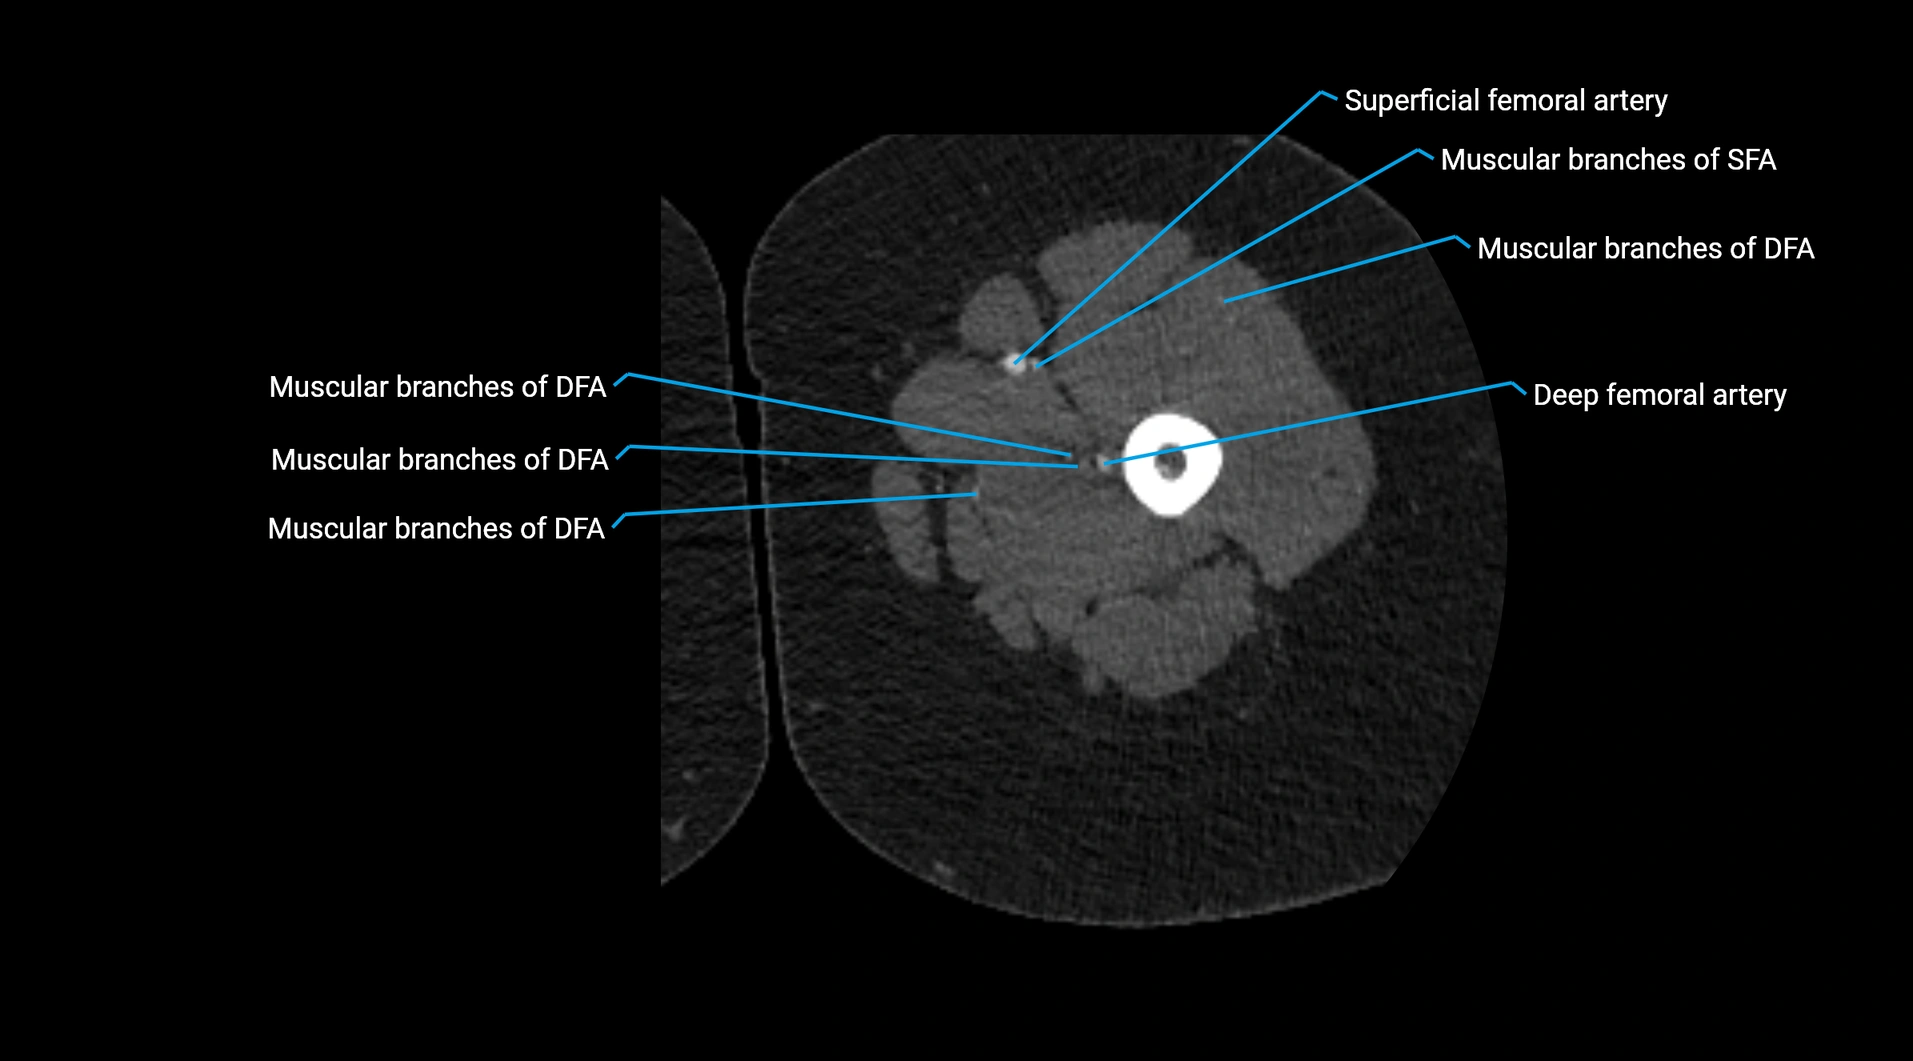

CT Appearance

Non-contrast CT:

• Appears as a tubular soft tissue structure anterior to vertebral bodies

• Calcified atherosclerotic plaques appear as hyperdense foci along the wall

• Useful for screening abdominal aortic aneurysm (AAA) size and mural calcification

Contrast-enhanced CT (CTA):

• Gold standard for abdominal aortic imaging

• Provides excellent detail of lumen, wall, aneurysm, thrombus, and branch vessels

• Multiplanar and 3D reconstructions help in aneurysm measurement, stent graft planning, and dissection evaluation

• Detects acute rupture, traumatic injury, or occlusion with high sensitivity